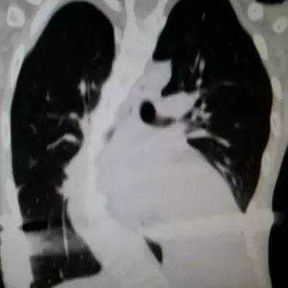

The patient was diagnosed with severe complex chest wall deformities accompanied by scoliosis. The heart was severely compressed and shifted to the left thoracic cavity.